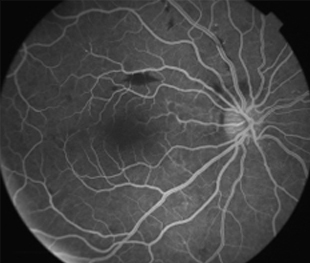

2 meses: disminución de manchas algodonosas y hemorragias con mejoría de circulación

Funcional

OD - 0,50 esf 0,9 +2

OI -0,25 esf 1,00

- Angiografía: teñido arterial, escape capilar, más tardíamente, no perfusion arteriolar y venular con teñido de las paredes vasculares y dilatación venosa.